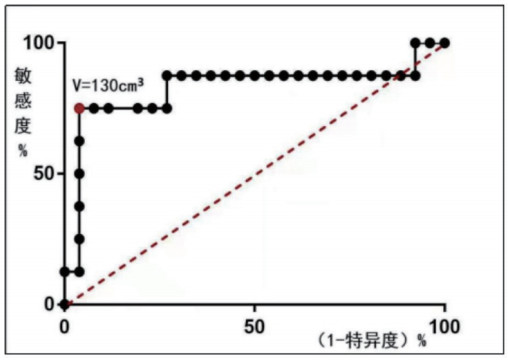

各组平均病灶大小(V)比较:组4的V显著大于组2、组3(P=0.036)。使用V预测治疗方案时当取V=130 cm3可获得最大约登指数(0.71),此时预测敏感度=0.75,特异度=0.96(图 2),提示V>130 cm3在UAE后需接受进腹手术治疗的概率明显上升。

| 图 2 病灶大小V(cm3)预测ROC曲线 |

UAVF的治疗方法包括观察、药物治疗、子宫动脉栓塞和手术治疗[17]。急诊大出血时,有生育要求者可行UAE,无生育要求者可行子宫切除术[9, 13]。目前的研究支持将UAE作为妇产科急症出血中替代手术的首选方法[18-19]。既往研究显示,治疗方式的选择与病灶大小及病灶收缩期峰值(PSV)相关,当子宫动静脉瘘PSV较高且病变较大时,UAE是理想的治疗方法,可反复多次进行[5, 20]。该研究中单纯UAE成功率达92.3%,相关并发症较少,对生育影响小,与文献报道相符[5]。但目前缺乏对病灶大小与治疗方法疗效的研究,潜在风险的PSV值亦无统一标准[5, 15]。本研究得出超声测量病灶大小(V)和最大径线(a)对该病治疗的意义及治疗节点:V>130 cm3或a>5 cm的患者行UAE后再进腹手术治疗(病灶剔除或子宫切除)安全有效,否则容易出现栓塞失败或病情反复。